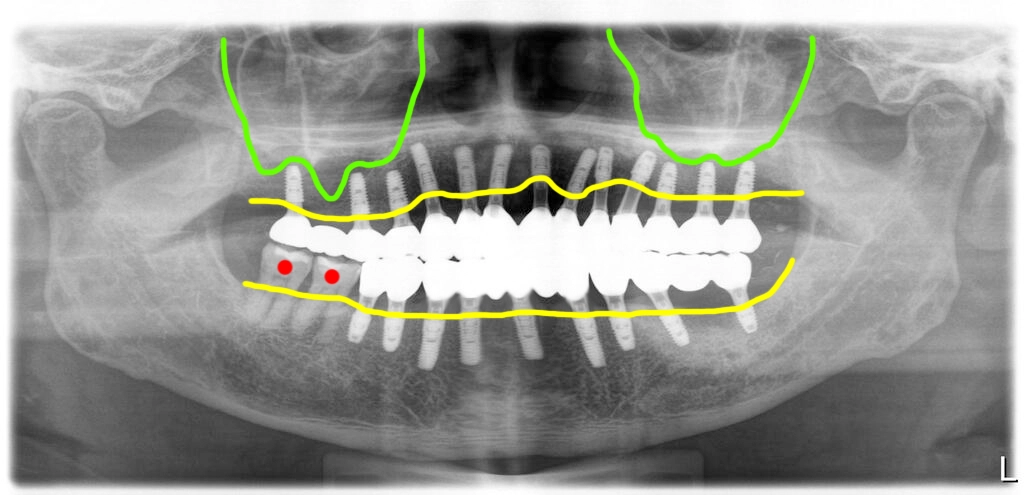

위 13개, 아래9개로

뼈이식없이 전체임플란트 완료

오른쪽 위쪽에는 뼈가 부족한 상태였지만 환자가 흡연을 하는 것을 감안해서 이용가능한 뼈에 간단한 뼈이식으로 바로 임플란트를 식립했습니다. 이렇게 하는 뼈이식의 경우 추가비용이 발생하지 않습니다.

발치하기로 한 치아들을 모두 염증과 함께 제거한 후 임플란트를 즉시 식립했습니다. 위에는 13개, 아래 9개 식립해서 수술당일 임시치아를 적용해 드렸습니다.

오른쪽 위 뼈가 많이 없는 부분 한 군데와 왼쪽 아래 염증이 심했던 부분 한군데를 제외하고는 일반적인 위치에 임플란트를 식립하였고, 초기고정은 모두 좋았습니다.